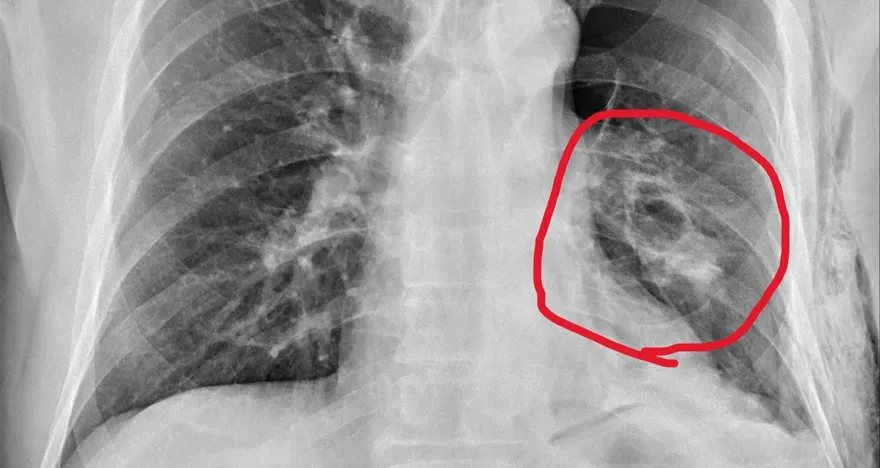

氣胸

血胸

肋骨內固定手術

連枷胸